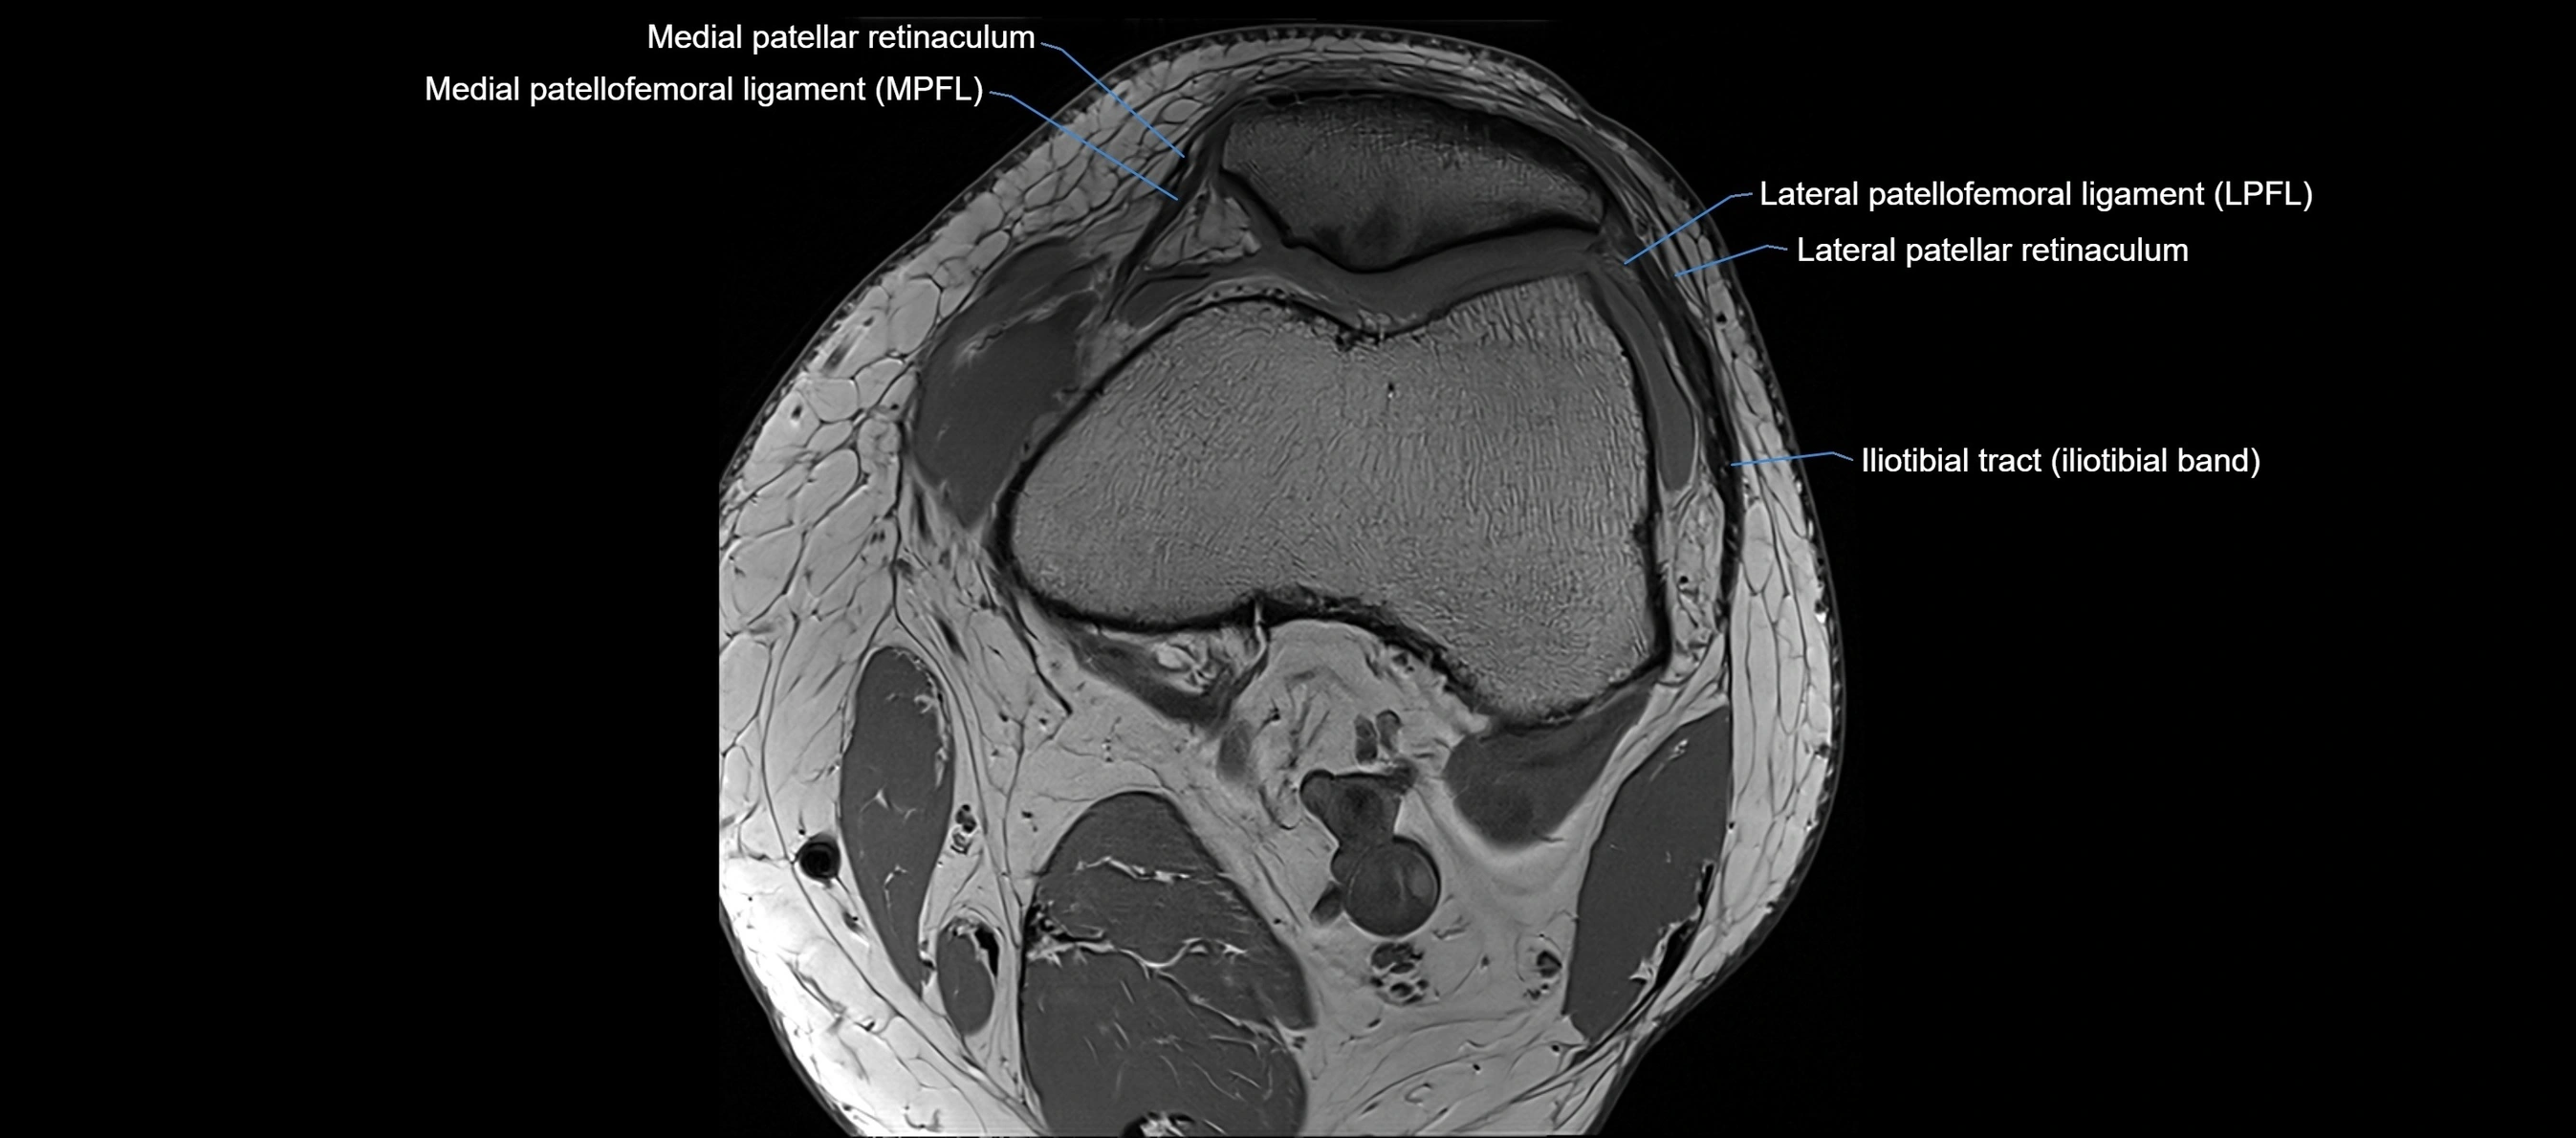

MRI images

image